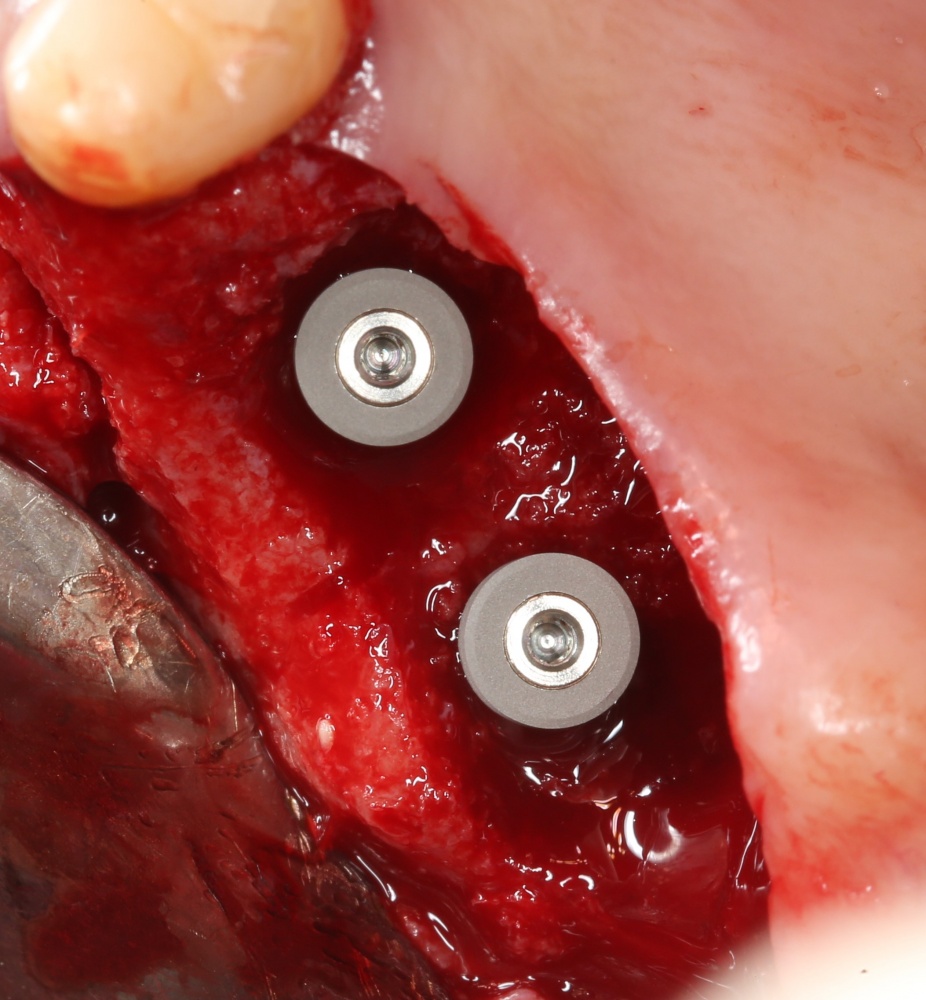

За фото не переживайте — эту пациентку мы вылечили))))